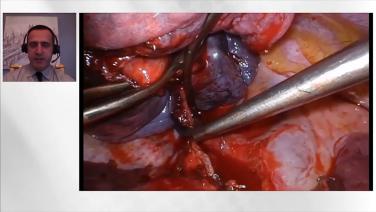

Thoracic Surgery Techniques & Approaches using Ultrasonic Energy with Zane Hammoud, MD

Ultrasonic Energy in VATS with Moishe Liberman, MD

Lobectomy Incision Location with Robert McKenna, MD

Left Lower Lobectomy Instruments with Scott J. Swanson, MD

Right Upper Lobectomy Demonstration with Robert McKenna, MD